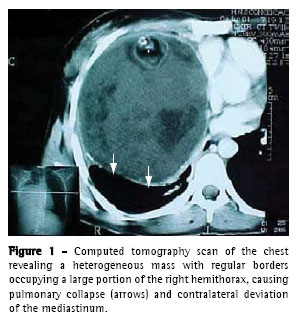

A 27-year-old, previously healthy female patient, a native and resident of Taquara (located in the state of Rio Grande do Sul, Brazil), sought treatment in her hometown due to chest pain and progressive dyspnea. A chest X ray performed in the emergency room revealed near total opacification of the right hemithorax. The patient was than submitted to an initial thoracentesis with the removal of 500 mL of purulent fluid, which raised the suspicion of pleural empyema. Based on these findings, the patient received antibiotic therapy and was referred to the Thoracic Surgery Unit of the Hospital Nossa Senhora da Conceição in the capital city of Porto Alegre. Upon admission, the patient was asymptomatic. The patient had no fever and reported having no fever in the preceding days. Since there was no radiological improvement, a computed tomography scan of the chest was performed, revealing a heterogeneous lung mass with regular borders. The mass was 10.1 x 11.7 cm in size and occupied the lower two-thirds of the right hemithorax but was not encroaching upon any of the adjacent structures (Figure 1).